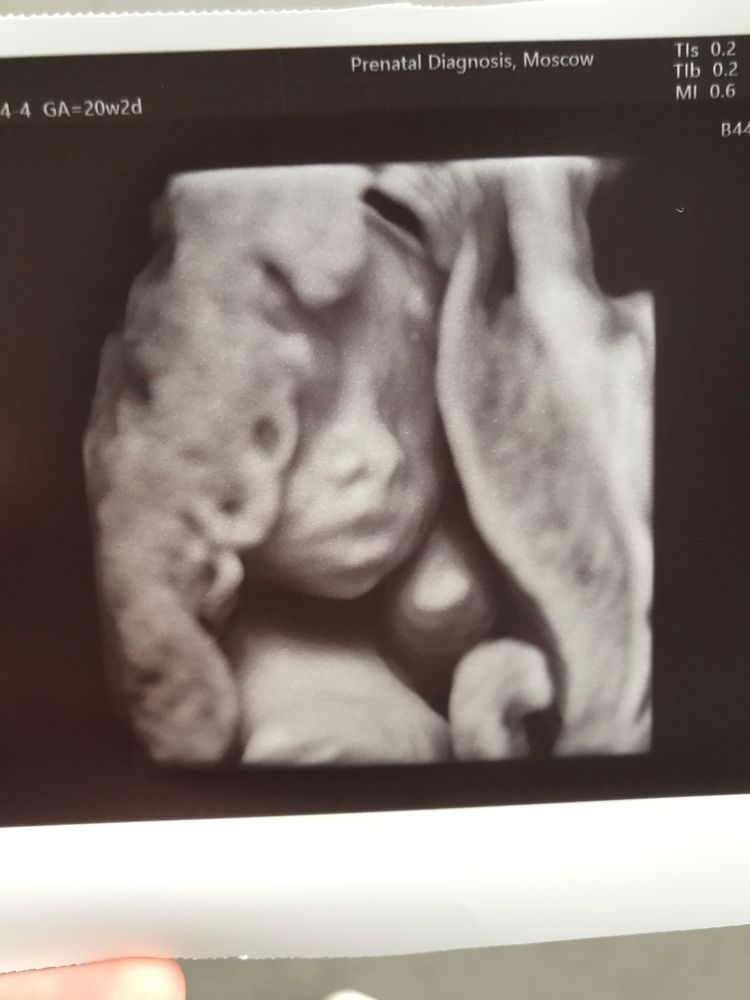

2 скрининг. Что-то я на панике 😅

У деточки все хорошо, воды хоть и по верхней границе, но в норме. Но весит, блин, деточка аж 417г, что есть 92% 😩

Мысли о ЕРпКС ушуршали в прекрасное далеко, с нетерпением жду сланную сегодня глюкозу, до этого все было в норме.

УЗИст пока не паникует, сказала переделать в 26-28 недель, можно скачок роста был…

Какое личико миленькое. Лапочка.

Возможно, это индивидуальная особенность - хорошо растет. И в третьем триместре замедляется рост. У меня пупс все скрининги вперед планеты шел по размерам и весу, а в третьем триместре замедлился, родился нормальным.

У меня тоже где -то с 20 недели ставили большой вес 98%.

сейчас на 38 неделе в норме